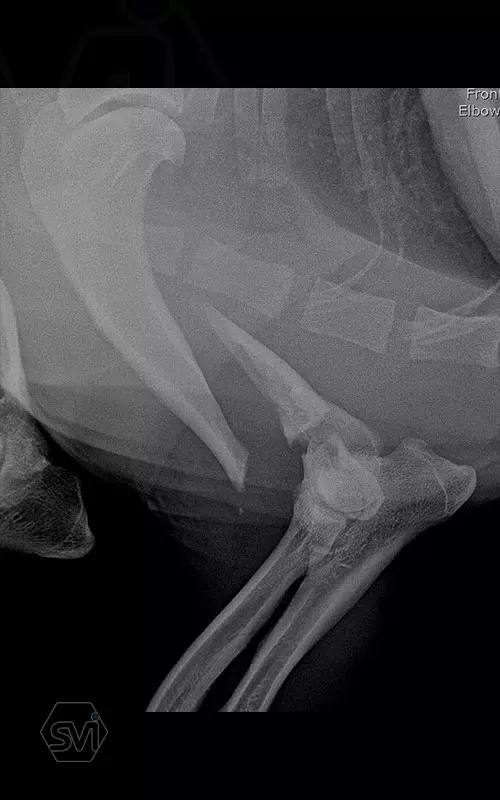

In our first case, we got right to the heart of it: we operated on a 2-year-old dachshund-type mixed dog weighing 9 kg, who overstretched his right humerus while stepping on pallets and suffered a Y-shaped humerus fracture that extended into the elbow joint combined with a large longitudinal splinter. To treat the fracture, we chose the new, cutable poliaxial locking plate, and immediately placed two, one medially and one caudolaterally. The intercondylar fracture and the longitudinal diaphysis fragment were each fixed with a 2.4 lag screw.